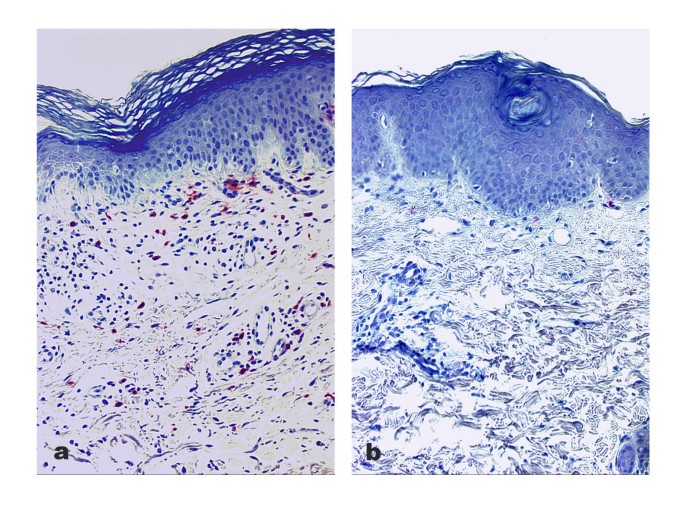

After three weeks of treatment the SCORAD score decreased significantly from 70.4 ± 13.1 to an average of 24.7 ± 12.1 (p < 0.0001). Prior to therapy an elevated percentage of cathepsin G+ cells, morphologically predominantly lymphocytes, could be detected within the dermal inflammatory infiltrate in AD. The enhanced staining distribution could be reduced after UVA1 phototherapy (Fig. 1a,1b).

Pre- and posttherapeutic labeling of cathepsin G in a representative patient with atopic dermatitis Cathepsin G immunostaining in skin biopsies of a representative patient with severe atopic dermatitis before (a) and after (b) treatment. Note the decrease of cathepsin G+ inflammatory cells (b) after 3 weeks of medium-dose UVA1 phototherapy with a cumulative dose of 750 J/cm2 (original magnification, × 200).

Referring to cathepsin G+ immunostaining before therapy, an average expression of 10.0% ± 0.051 within the 1st field, 7.3% ± 0.059 within the 2nd field and 6.8% ± 0.077 within the 3rd field was assessed. Taken together, the percentage of cathepsin G+ cells was determined at a mean grade of 8.0% ± 0.054 in sites of perivascular infiltration in patients with AD (Fig. 1a, Fig. 2). After medium-dose UVA1 phototherapy, a significant reduction of cathepsin G+ cells towards a mean percentage of 5.3% ± 0.044 within the 1st, 4.2% ± 0.039 within the 2nd and 2.6% ± 0.040 within the 3rd field below the junction could be observed. The total average percentage of inflammatory cells stained positive for cathepsin G immunolabeling was 4.1% ± 0.031 (p = 0.001; Fig. 1b, Fig. 2). Simultaneously, cathepsin G+ cells were counted with a mean of 8.8 ± 7.1 per field before and 4.7 ± 4.1 after the UVA1 phototherapy.